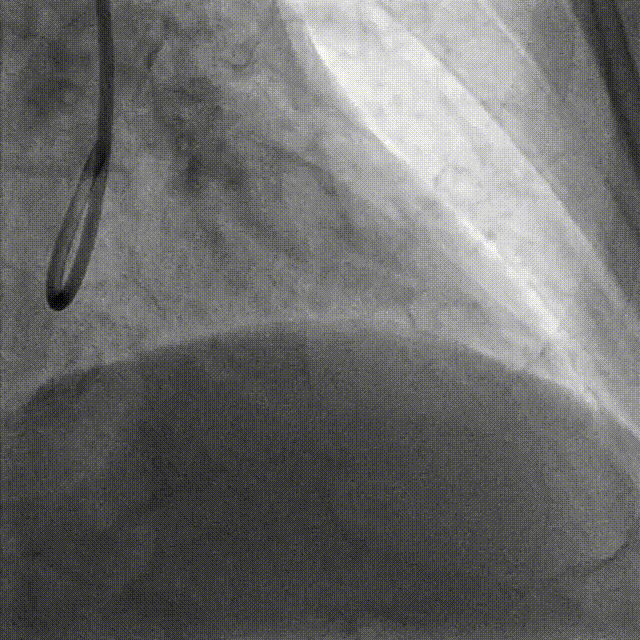

PCI-RCA TR, 7F JR4.0 ROTA with 2.0mm burr

Angiography post-ROTA

Lesion preparation NC 2.5*12mm → Cutting balloon 4.0*10mm @ 12atm